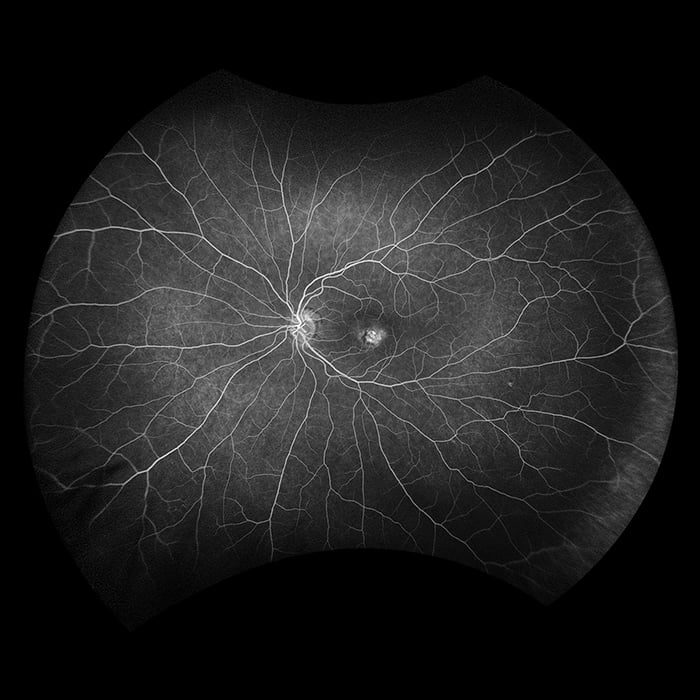

Optos führte die UWF™ (Ultra-Weitwinkel Bildgebungstechnologie) ein mit der Augenärzte Augenpathologien entdecken, diagnostizieren, dokumentieren und behandeln können, die sich zuerst in der Peripherie zeigen und mit konventionellen Untersuchungsmethoden und Geräten zunächst unentdeckt bleiben können. Jedes unserer Geräte für hochauflösende Ultra-Weitwinkel-Bildgebung erfasst mittels Laser Scanning Technologie in einer einzigen Aufnahme mehr als 80 % bzw. 200° der Netzhaut. Eine vollständige Liste unserer Geräte mit Ultra-Weitwinkel Bildgebungstechnologie finden Sie unten.

Silverstone RGB setzt neue Maßstäbe in der Netzhautbildgebung. Es ist das einzige Gerät, das in einer einzigen Aufnahme farbgetreue 200°-optomap-Ultraweitwinkelbilder erfasst - mit einem nahtlos integrierten, geführtem Swept-Source-OCT. Zum ersten Mal können Augenärzte in einem Gerät auf neun aussagekräftige Bildgebungsmodalitäten zugreifen, die jeweils für die Darstellung von Pathologien in der gesamten Netzhaut ausgelegt sind.

optomap verbessert nachweislich die Erkennung von Pathologien, das Management von Erkrankungen und Arbeitsabläufe in Praxen und Kliniken. Mit nun neun Modalitäten zur Netzhautbildgebung, darunter integriertes peripheres Swept-Source-OCT, erleichtert Silverstone RGB die Untersuchung der Netzhaut vom Glaskörper bis zur choroidal-skleralen Grenzfläche.

- Fluoreszenzangiographie